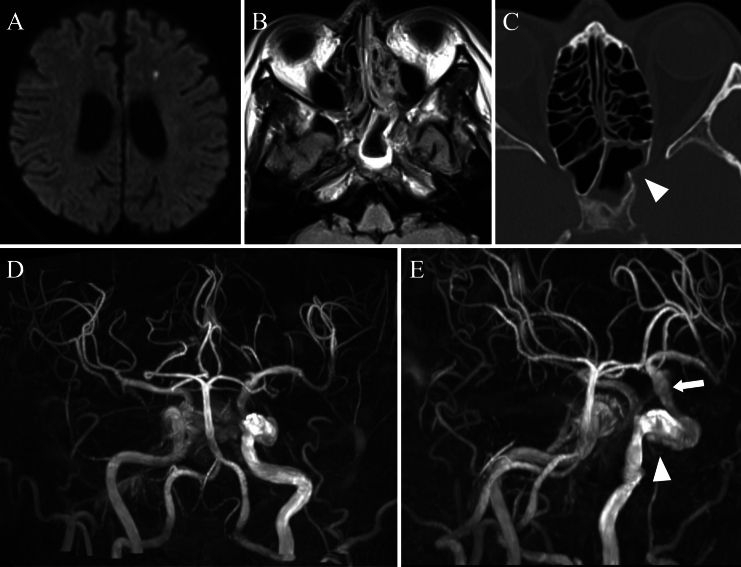

Observations: A 56-year-old man with poorly controlled diabetes experienced a sudden loss of vision in his left eye. Cranial imaging revealed invasive sphenoid sinusitis and CCF attributable to a ruptured infected CCA, as well as an unruptured infected supraclinoid internal carotid artery (ICA) aneurysm. After 3 weeks of medical treatment, the patient developed sudden impairment of higher function. MRI revealed occlusion of the distal ICA attributable to thrombosis of the supraclinoid ICA aneurysm. The anterior circulation was perfused from the contralateral side via the anterior communicating artery. Proximal occlusion with coils was performed, leading to ablation of the CCF.